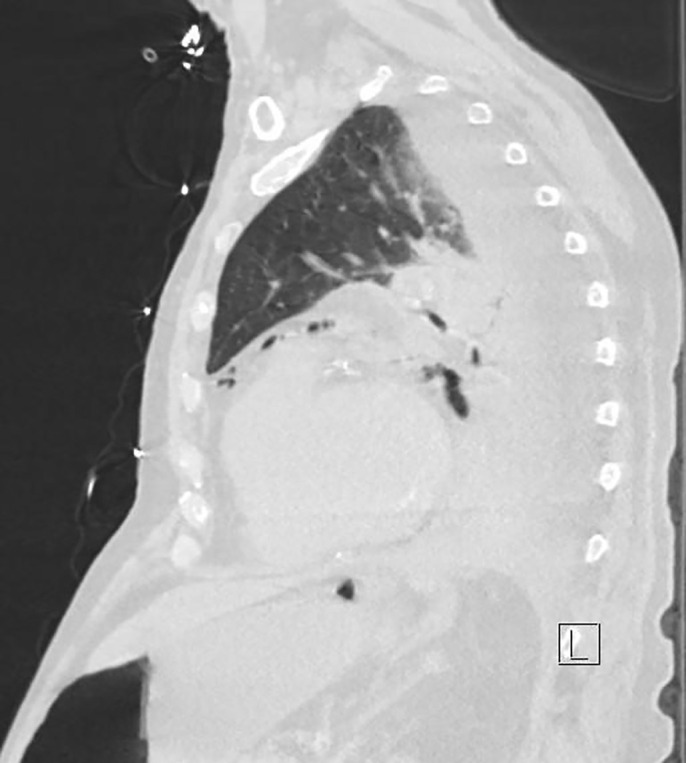

Case description: This report presents a 76-year-old man who presented to the emergency department after a history of several syncopal episodes and was found to be in complete heart block. Two days later, he acutely developed abdominal distention and coffee ground emesis. As the medical team was able to gather more history from the patient and his family, it was revealed that he had associated vomiting with his episodes of syncope. CT scan of the abdomen and pelvis demonstrated pneumomediastinum concerning for esophageal perforation. His clinical status subsequently deteriorated. He was intubated and a temporary transvenous pacer was placed before being transferred to our facility for emergent surgery.